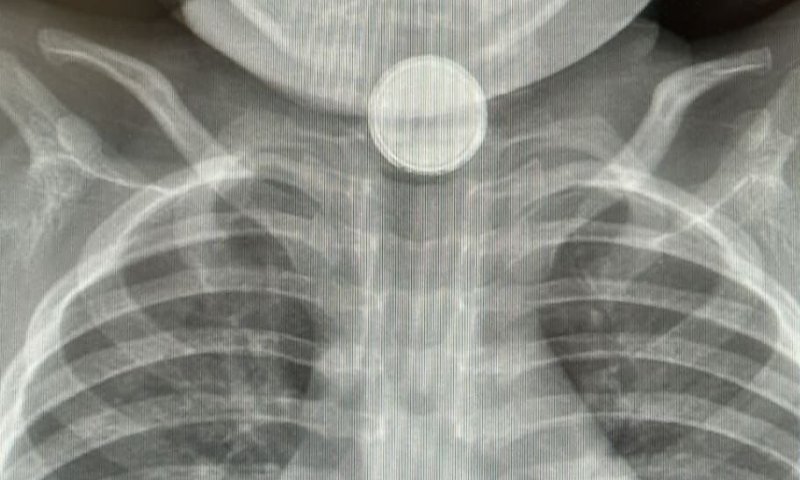

בליעת סוללות בקרב ילדים, בעיקר בגיל הרך, היא תופעה מסוכנת הדורשת התערבות רפואית מיידית. לרוב מדובר בסוללות כפתור קטנות ונפוצות, המצויות במגוון מכשירים ביתיים כגון צעצועים, שלטים ומפתחות רכב.

סוללה שנתקעת בוושט למעלה מ-20 דקות עלולה לגרום לתגובה כימית מהירה ולפגיעה חמורה ברקמות תוך זמן קצר. החומרים הכימיים האגרסיביים שבסוללה חודרים לרקמות ועלולים להמשיך להתפשט במשך שבועות, ואף יותר מחודש לאחר הוצאתה, לעבר כלי הדם הסמוכים – תהליך המסכן את הילד לנזק ממושך ואף לדימום פנימי מסכן חיים.

כך למשל, במקרה חמור שאירע לאחרונה, בן כשנתיים הובהל לחדר ההלם במחלקה לרפואה דחופה ילדים כשלושה ימים לאחר שבלע סוללה. הוא נזקק לניתוח חירום, ובשלב זה טרם ברורה חומרת הנזק שנגרם, אשר עלול להיות בלתי הפיך. במקרה אחר, בת 7 הובהלה למיון כשעה וחצי לאחר הבליעה, אך נזק משמעותי לוושט כבר נגרם. היא מאושפזת לאחר שהחומר הכימי החל להתפשט לעבר כלי הדם הסמוכים, באופן המעמיד אותה בסכנה לדימום פנימי, וייתכן שתזדקק לניתוח נוסף.